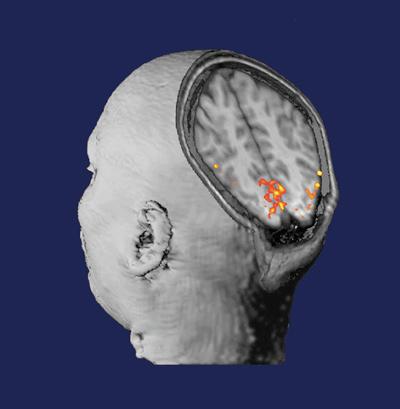

“Steve did the complete Martinos workup,” Dr. Rosen says, “an MEG study, a PET-MR study and a Connectome study. The goal was to try to understand both the nature of the brain lesion that she had — the cause of the epilepsy — and how the adjoining parts of her brain may have been involved.”

The latter was important because resection of a brain lesion can also extend to the surrounding areas, thus impacting the functions associated

with those areas. Understanding the wiring of Kristine’s brain would help determine which of the connections the neurosurgeon would want to preserve in treating her epilepsy.

With the additional information from the imaging studies, Dr. Stufflebeam worked with the neurosurgeon to come up with a surgical approach in which the margins of the lesion were much better delineated than they would have been otherwise. “Based on this information, they felt confident they preserve her cognitive function,” Dr. Rosen says. “They did the surgery and that’s largely what happened.”